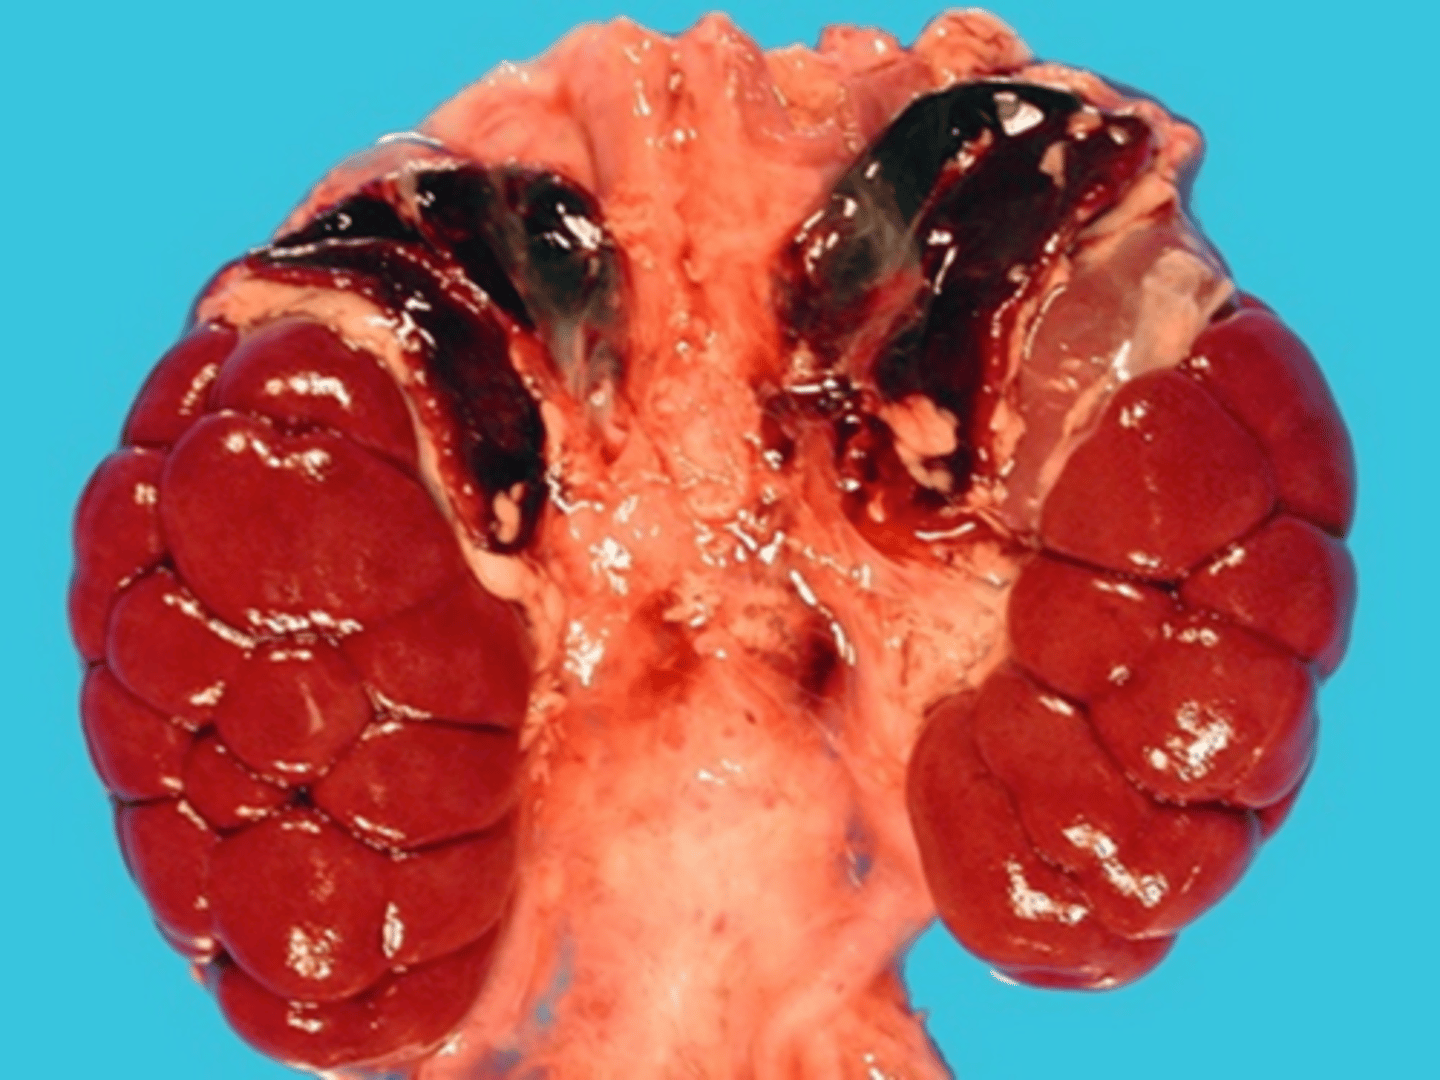

Adrenal Hyperplasia

Identify the pathology